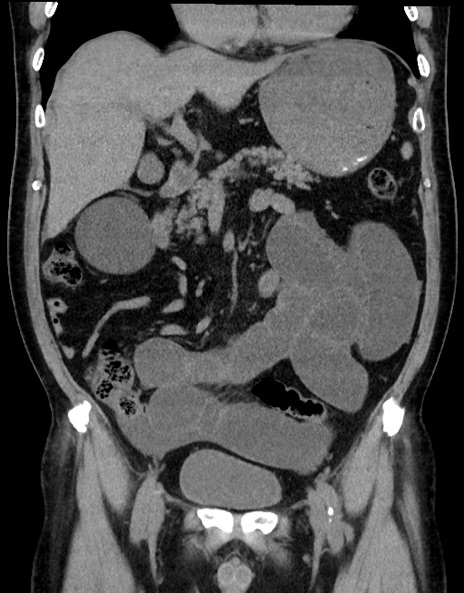

症例15(冠状断像)

【症例】70歳代男性

【主訴】腹痛

【現病歴】今朝から腹痛あり。全体的に痛い。特に左上の方。排ガスが今日はない。冷や汗が出る。

【既往歴】直腸癌術後

【身体所見】左側腹部〜上腹部に圧痛あり。腹膜刺激症状明らかなではない。軽度反跳痛。左下腹部に術後瘢痕あり。

【データ】WBC 7700、CRP 0.02